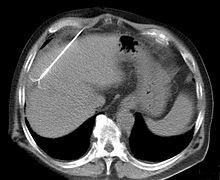

CT scan showing radiofrequency ablation of a liver lesion

RFA may be performed to treat tumors in the lung,[6][7][8] liver,[9] kidney, and bone, as well as other body organs less commonly. Once the diagnosis of tumor is confirmed, a needle-like RFA probe is placed inside the tumor. The radiofrequency waves passing through the probe increase the temperature within tumor tissue and results in destruction of the tumor. RFA can be used with small tumors, whether these arose within the organ (primary tumors) or spread to the organ (metastases). The suitability of RFA for a particular tumor depends on multiple factors.